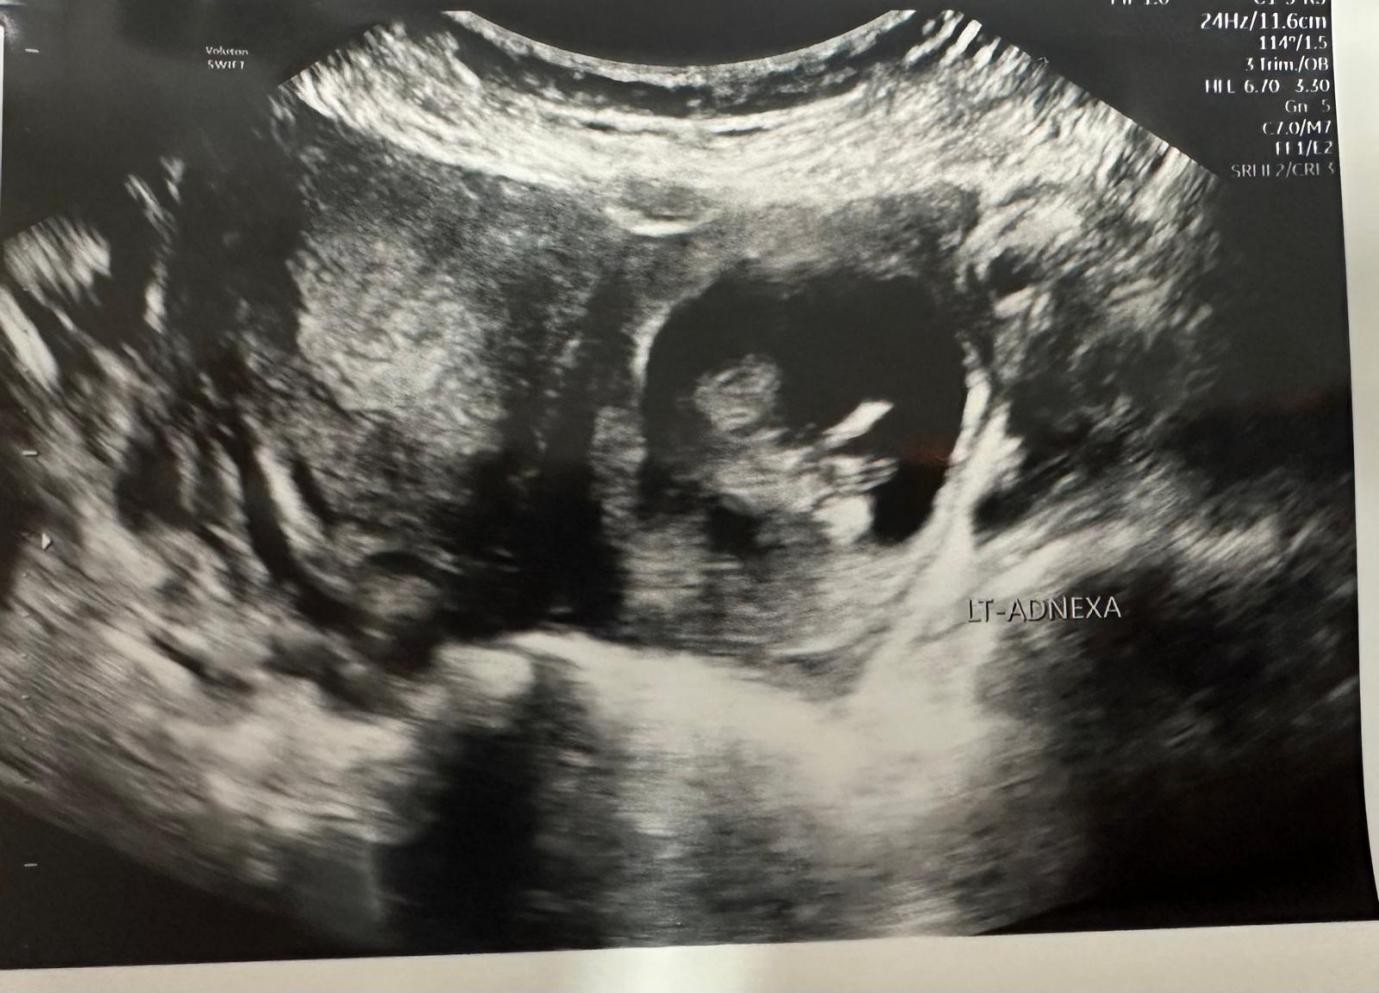

Her abdomen was mildly tender on examination with voluntary guarding. A transvaginal Ultrasound showed a viable intrauterine pregnancy at 12+4 weeks and another viable left tubal ectopic pregnancy of 11 weeks + 6 days gestation. She underwent laparoscopic surgery where a small amount of bleeding was seen in the abdomen, and an ectopic mass in the left adnexa. This mass was removed safely using Ligasure. The procedure was uncomplicated with 100mls of blood loss. She had a bedside USS post-op op which confirmed a viable intrauterinepregnancy.

Figure 2